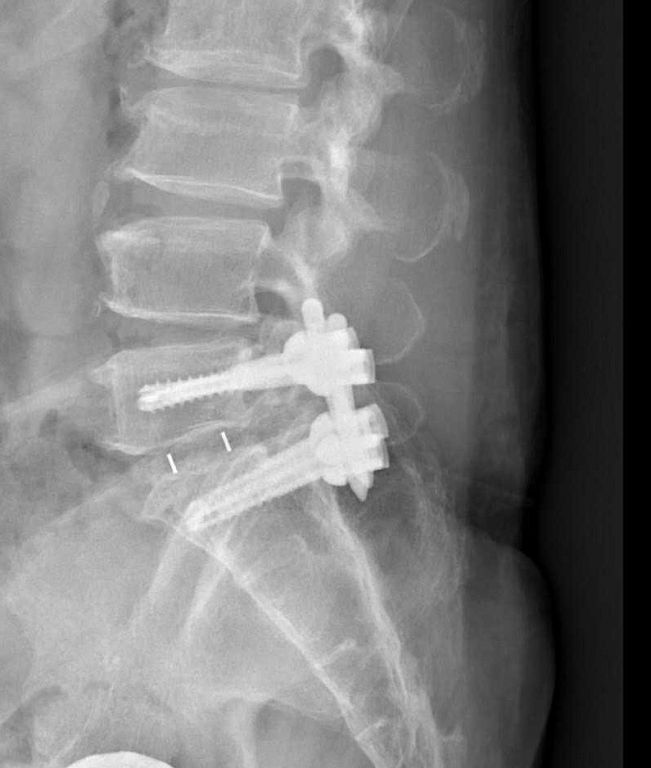

影像檢查顯示,張先生的第五節腰椎椎弓骨折合併脊椎解離。洪祥益主任表示,這類病人多半表現為腰痠背痛、久坐久站困難,通常可先藥物治療觀察,但相較於其他類似問題的病人,張先生疼痛異常明顯,手術中發現脊椎關節內長滿痛風石,這些痛風石如白色黏稠物般,附著在神經與關節縫隙間,若不清乾淨,就會持續引發神經發炎與疼痛,甚至比坐骨神經痛更強烈。團隊透過顯微鏡,在不傷及神經的情況下,仔細將痛風石刮除清理,再以微創固定融合手術完成治療。